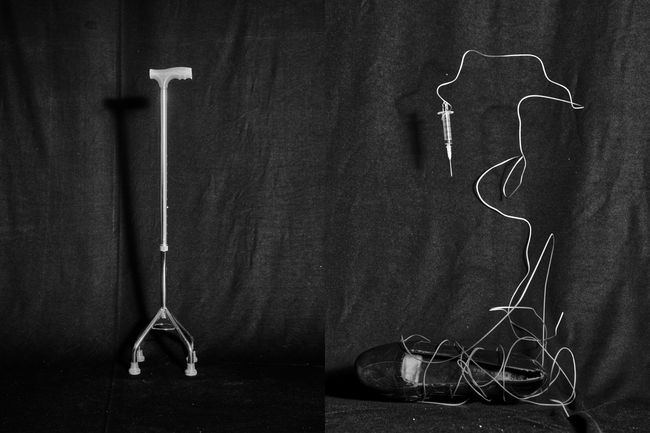

In There Is No Other Home I explore Still-Life, text, sculpture and mixed media experiments to address the Non-Linearity of Healing, and depict healing as a loop. Using staged photography I reflect on how trauma rewires both memory and body. The images move between absence and presence, rupture and repair, exploring the tension of detachment and reattachment to one’s own body.

There Is No Other Home emerges from the space between chaos and understanding. My body often feels like it carries its own memory. My hands loose grip, I stumble more often, and I freeze at things others take for granted, like driving. I return to fragments of memory, my mother’s CT scan when she was carrying me and my twin sister, a childhood photograph, not as evidence of illness but as traces of fragility, endurance, and survival.

Working with hands became central. Sensations of tingling in my fingers was the first sign of my illness, so I sculpted and cast hands as a way to confront the absence of movement.

In this process of self-discovery, camera became both my weapon and my shield. I reimagine Photography as a tactile language of healing, a space to witness, question, and accept the scattered parts of self. There Is No Other Home reveals the paradox of art as both a form of control and a confrontation with chaos, where making becomes a physical encounter with trauma and healing. The hands I sculpted became more than metaphors, they turned into a tangible form of trauma, making visible what is normally invisible to the eyes.